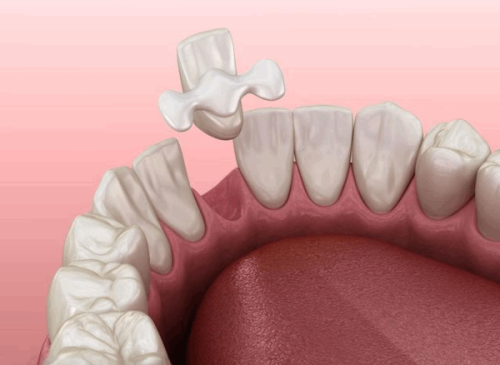

补牙手术所用填充材料

补牙时使用的填充材料也会影响补牙成效的维持时间。不同的填充材料具有不同的特性和使用寿命。一般来说,质量较好、性能稳定的填充材料,其维持时间相对较长。例如,树脂材料是目前比较常用的补牙材料,它的美观度和耐磨性都不错,能维持较长时间;而银汞合金虽然强度较高,但美观性较差,使用年限也会受到一定影响。在选择填充材料时,患者可以根据自己的需求和经济状况,在医生的建议下做出合适的选择。